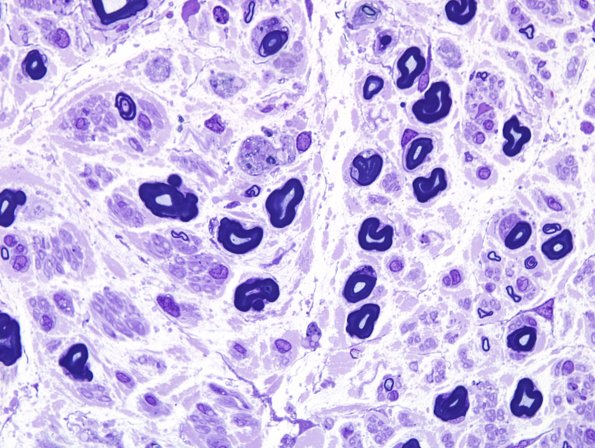

Washington University Experience | PERIPHERAL NEUROPATHY | 13 POEMS SYNDROME | 4A3 POEMS (Case 4) Plastic 100X 2.jpg

4A3,4 Higher magnification images show axonal degeneration and confirm the general loss of small and large myelinated axons.(Plastic sections)